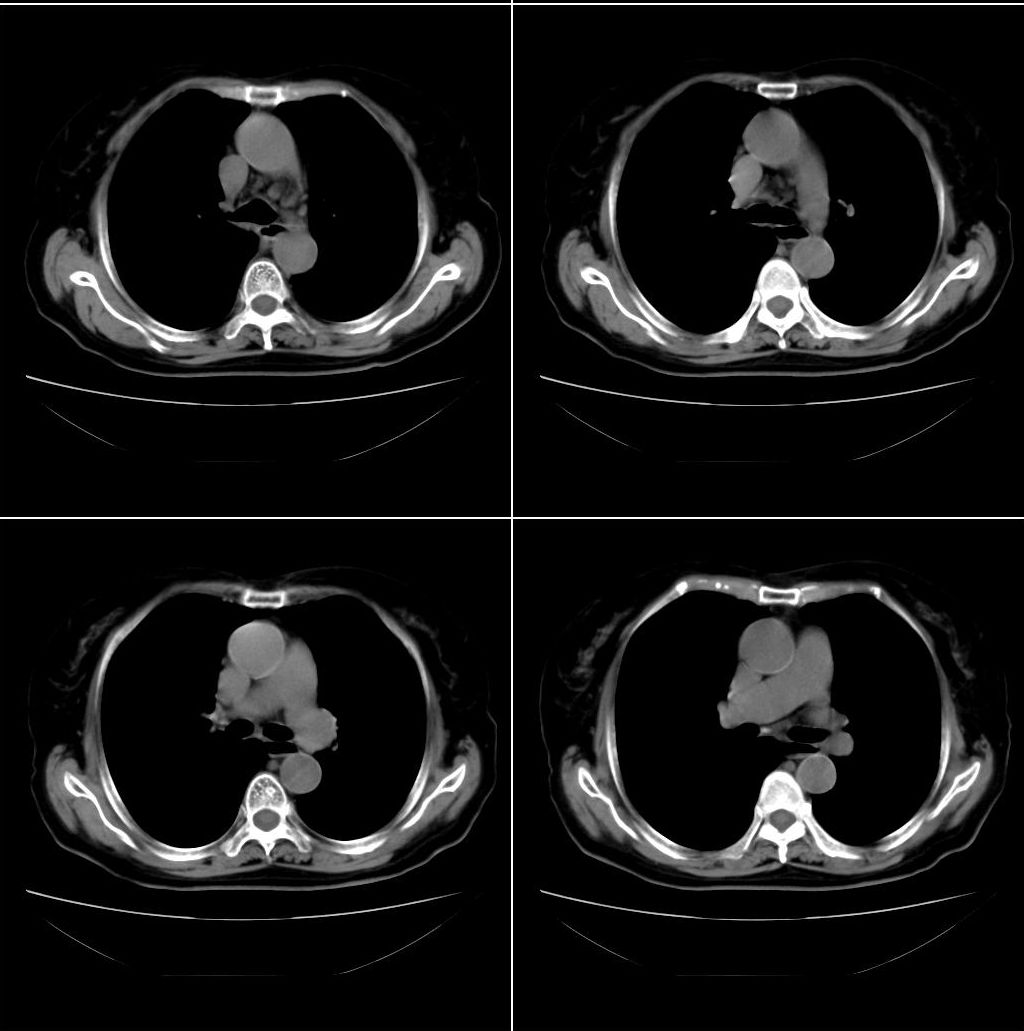

以下是引用zhangxu5888在2007-12-22 20:56:00的发言:[br]食道病变???纵隔淋巴瘤?

以下是引用卜一在2007-12-22 22:44:00的发言:[br]纵隔占位,支持:气管源性肿瘤!

以下是引用sxlcbc在2007-12-23 4:27:00的发言:[br]气管源性肿瘤觉得有点不靠谱啊,看上去气管是受压改变的。更像是上段食管的改变,周围淋巴结肿大,食管受压。看看以下六幅图片:[br]不过,有一点不好理解:食管肿瘤应该有食道症状的,再说食管癌出现周围这么大的淋巴结也不多见啊,如果考虑淋巴瘤倒是更合理一点,这样气管,食管受压改变也许更合理一些。[br][br]